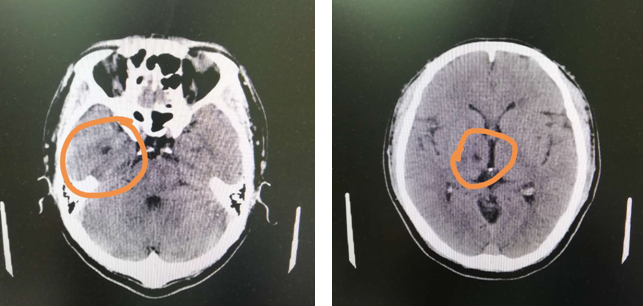

在徐主任的建议下,张师傅做了头颅CT,检查提示:两基地节区、右侧丘脑腔隙性脑梗塞,副鼻窦炎,脑干腔隙性梗塞不能排除。好在徐晓欣主任经验丰富,迅速联系将张师傅转入内科,张师傅的脑梗得以及时治疗。